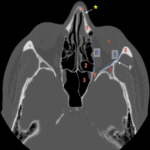

Giải Phẫu CT Mũi Xoang | Bài giảng CĐHA

Hình ảnh giải phẫu CT mũi xoang.